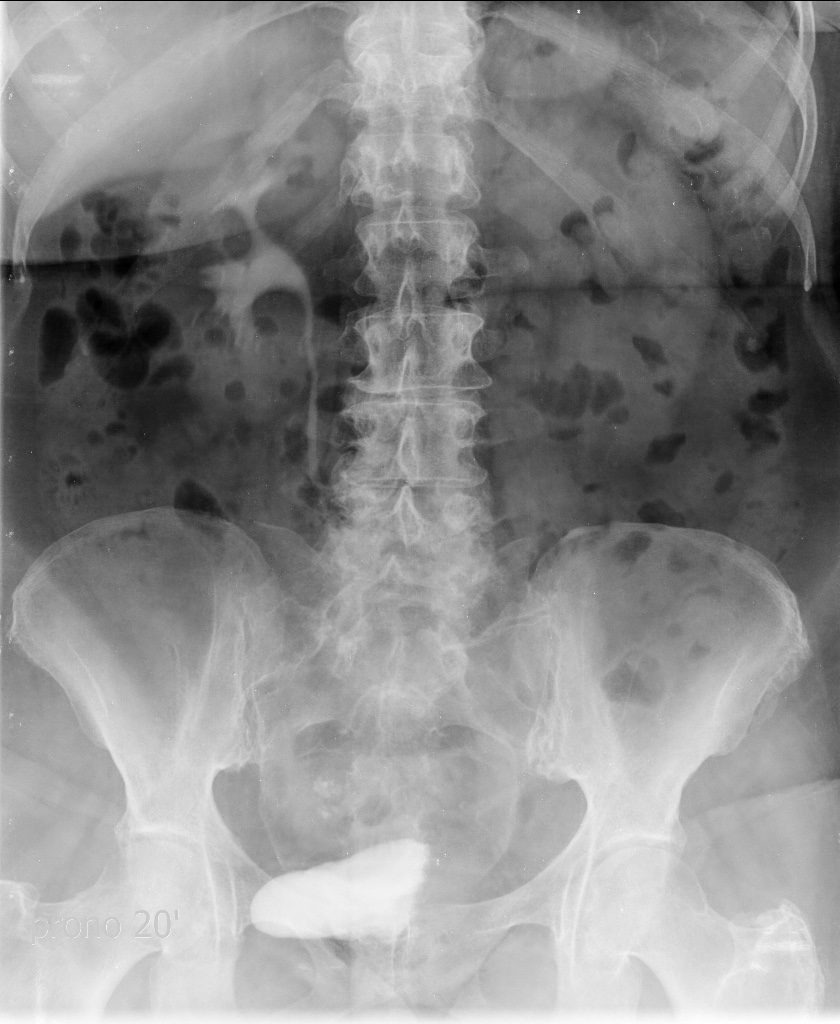

Se le realiza una Uro-Tc por seguimiento al año, aunque en esta ocasión el paciente refiere episodio de hematuria.

Tras el tratamiento de la recidiva y nefrostomía para la hidroureteronefrosis, vuelve acudir al hospital a los 9 meses por episodio de dolor en FD y malestar general. Se realiza una ecografía de urgencias.

Se realiza nueva TC bifásico abdominopélvio y Uro TC.

- Ha desarrollado un tumor metacrónico en pelvis renal derecha, también responsable de la hidroureteronefrosis.

- Mala evolución radiológica del proceso a expensas de metástasis pulmonares y hepáticas.